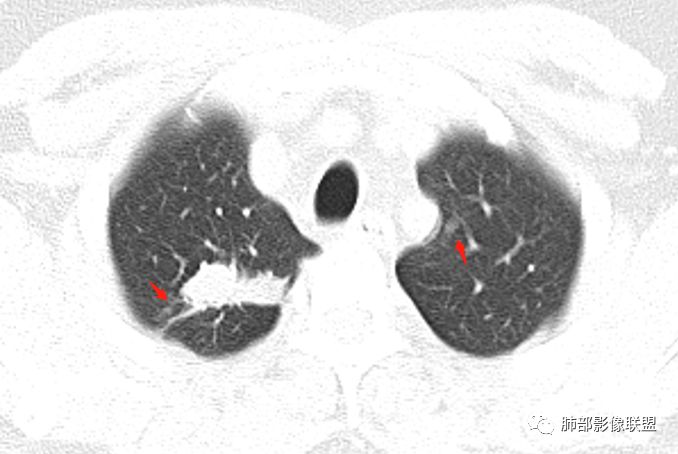

患者中年男性,主诉:咳嗽  胸痛。  胸CT:右肺上叶尖段占位,病灶位于支气管外,病灶周围部分区域可见毛玻璃影,病灶边缘不规则,部分区域可见平直,胸膜牵拉(无胸膜凹陷),柔软长毛刺,分叶,纵隔窗病灶没可见低密度区,左肺尖可见一点状病灶,病灶整体考虑良性疾病:感染性病变(结核?),感染后机化?。恶性病变待除外。

右肺上叶结节,边缘平直为主,病灶比较散,周周似乎有卫星病灶,边缘有胸膜牵拉,从粗到细,左肺尖奕有卫星灶,综合考虑结核。

晨读:患者中年男性,反复咳嗽1月余,伴左胸部疼痛1周就诊。胸部CT:右肺上叶尖后段不规则结节,见长毛刺、胸膜牵拉、条索影,周围见卫星灶。未见明显淋巴结肿大,符合结核病变。鉴别其他。但其病灶位于右肺,主诉左胸痛,是误写,还是?

一米阳光:    晨读,右上肺结节影,形态不规则,边缘平直,部分凹陷,长软毛刺,胸膜牵拉,周围卫星灶。考虑结核。鉴别腺癌,部分边缘彭隆

傅昌瑜:  男,49岁,反复咳嗽1月余,伴左侧胸痛1周。右肺上叶尖段结节,边缘平直、凹陷,周周似乎有卫星病灶,边缘有胸膜牵拉,从粗到细,左肺尖见小点状病灶,考虑良性病变,结核可能性大。

小飞:  晨读:右肺上叶不规则结节灶,沿支气管走形分布,边缘平直,U型凹陷,脊柱侧有少许磨玻璃影,左肺尖少许斑点灶,综合考虑结核。

影像,气管憩室,两肺尖都有病灶,长索条

右肺上叶病灶两部分

左肺尖及右肺病灶附近见小斑点,边界尚清

1、病灶整体形态不是类圆形,边缘凹陷、平直为主,长轴重建可能更明显,长索条,附近卫星灶,左肺尖有类似小高密度影;按常规:首先要考虑结核